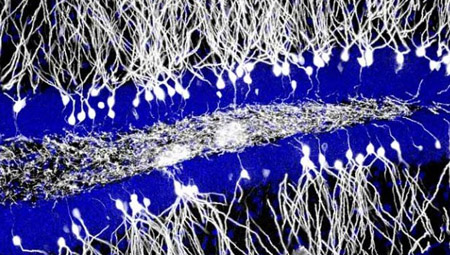

![]() 大部分人都希望能过目不忘,但遗忘几乎是必然发生的生物学现象,学习记忆力好似乎是聪明的主要表现,其实遗忘也很重要,选择性遗忘是保持大脑功能的有效手段,这就像是电脑的内存和硬盘一样,要随时清理甚至删除,才能更有效继续工作。过去科学家对学习记忆产生的原理了解比较多,但是对遗忘这种生物学现象真的了解部多,尤其是细胞和分子细节。 你可以记住你的生日,但你能记住数周前早餐吃过的东西吗?大多数人来说,日常小事会被逐渐遗忘。最近研究提供了一种解释遗忘这种现象的神经生物学机制。研究发现,在海马齿状回新生神经细胞可帮助删除老的记忆,并提供新的记忆载体。 人和许多哺乳动物如小鼠,出生后大脑大部分区域都失去再生能力,但在一些负责记忆编码的脑区,这种神经再生能力始终保持着,这些区域就包括海马齿状回。在人类大脑,每天海马齿状回都能制造700个新的神经细胞。 研究发现,抑制小鼠神经再生会损害模式分离patternseparation的学习能力,模式分离是能对两种很类似环境区分的能力。 虽然关于神经再生和学习记忆的关系存在争议,但近10年大量研究支持,运动和药物(如抗抑郁药Prozac)促进神经再生的同时,确实能提高学习地点和时间知识的能力。数年前,加拿大神经生物学家PaulFrankland注意到他,但使用促进神经再生的干预后,他的一些实验动物似乎对某些需要记忆的工作任务出现困难。尤其是需要对细节进行记忆对任务。 这一些结果实在太有意思了,难以让Frankland遗忘。人类和小鼠从新生儿、青少年到成年,随着年龄增加神经再生能力逐渐减少,Frankland等尝试从神经再生角度来解释普遍存在的一个现象:婴儿期失忆,婴儿期失忆是指人成年后无法记忆2-4岁前的经历。一些理论模型认为,新神经细胞会通过破坏海马中已经形成的记忆信息,但是这种模型并没有任何活体证据。 为验证这个假说,Frankland等首先比较了成年会出生后17天等小鼠的记忆稳定性,17天的小鼠和人类1岁婴儿类似。将这些动物离开熟悉的(木屑隔音罩)环境,放到一个用金属底板的盒子内,并进行电击足底(很痛苦的刺激),然后把这些动物放回笼子内。第一次电刺激6周后,再次将这些动物放回电击足底的盒子内,但这次并不进行电击(只恐吓它们)。成年动物们能继续对这个环境保持恐惧表现(僵freeze)1月以上,年轻的老鼠第2天就忘记这个经历,就像没有发生过一样。Frankland说,少年能记忆24小时,然后就忘记了。这大概就是“少年不知愁滋味”和“新生牛犊不怕虎”的实验证据吧。 然后,他们对这些动物大脑内神经再生的情况进行分析(这不是已经确定的事情?),或许能找到婴儿小鼠不能长时间记忆的依据。考虑到运动能增加神经再生50%以上,科学家让成年小鼠进行转轮运动,这些动物每晚行走5公里路程。另外对这些动物注射一种抗抑郁药物Prozac,这种药物能促进神经再生100%左右。然后再对这些动物进行同样电击和其他类似记忆实验,结果发现这些动物也变得很容易忘记。他们的文章今天在线发表在《科学》上。 从技术上考虑,完全中断新生小鼠神经再生比较困难,但他们依靠基因工程技术让新生神经细胞自杀可抑制50%的神经再生。这些神经再生被抑制的婴儿小鼠也可以和成年小鼠一样表现出比较强的记忆能力。对电击的痛苦经历的记忆时间可以从1天不到,延长到1周左右。 心理学家长期认为,遗忘是人类精神健康的关键,但神经科学家不太关心这个问题,他们更多注意学习和记忆能力的研究。虽然现在不能完全确认,某些抗抑郁药物所以有用,或许就是通过促进神经再生,加快记忆删除程序,让患者将不愉快尽快遗忘,恢复傻呵呵的幸福生活状态。 但是由于目前我们对人类大脑的神经再生无法进行观察,所以难以了解人类是否也存在类似的过程。而且神经再生和记忆也可能存在正面联系,如果从再生角度,老年人已经很少再生了,恰好他们也是短期遗忘的更明显。这就存在完全相反的证据了。不过,这一研究是非常有意思的研究。 |